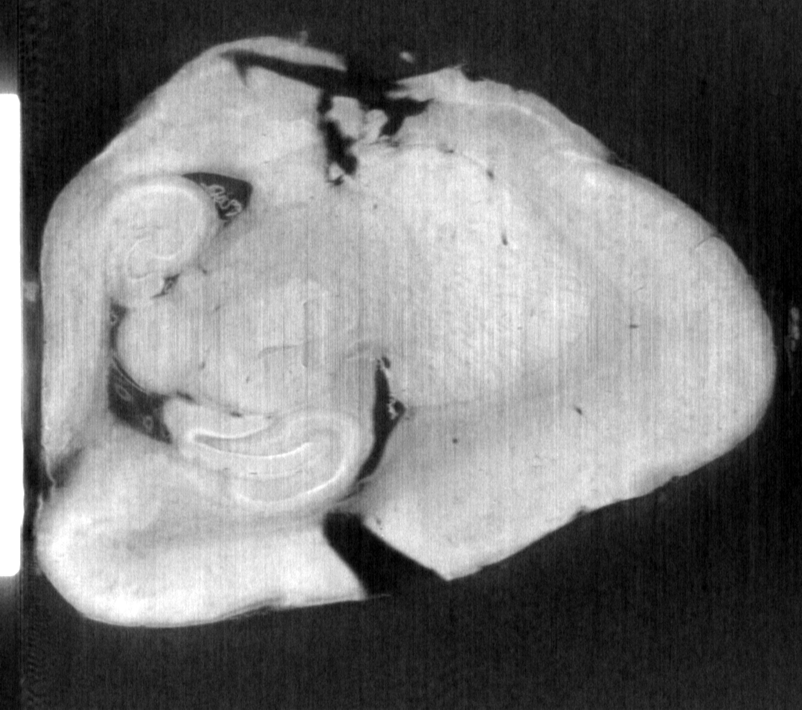

ラット尾

屈折コントラスト法(DEI)

17.8 keV

15分

試料提供:北里大学Lwin准教授